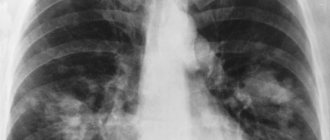

Именно споры этого грибка провоцируют болезнь – аспергиллему тканей легких. Так, споры грибков сначала попадают в носоглотку, затем перемещаются к бронхам и другим органам дыхания.

Главная опасность в том, что споры стремительно развиваются

Жизнедеятельность колоний способствует выделению опасных веществ, из-за которых на тканях формируются некротические очаги. Со временем эти очаги увеличиваются, ткани легких отмирают, что провоцирует удушье и летальный исход.